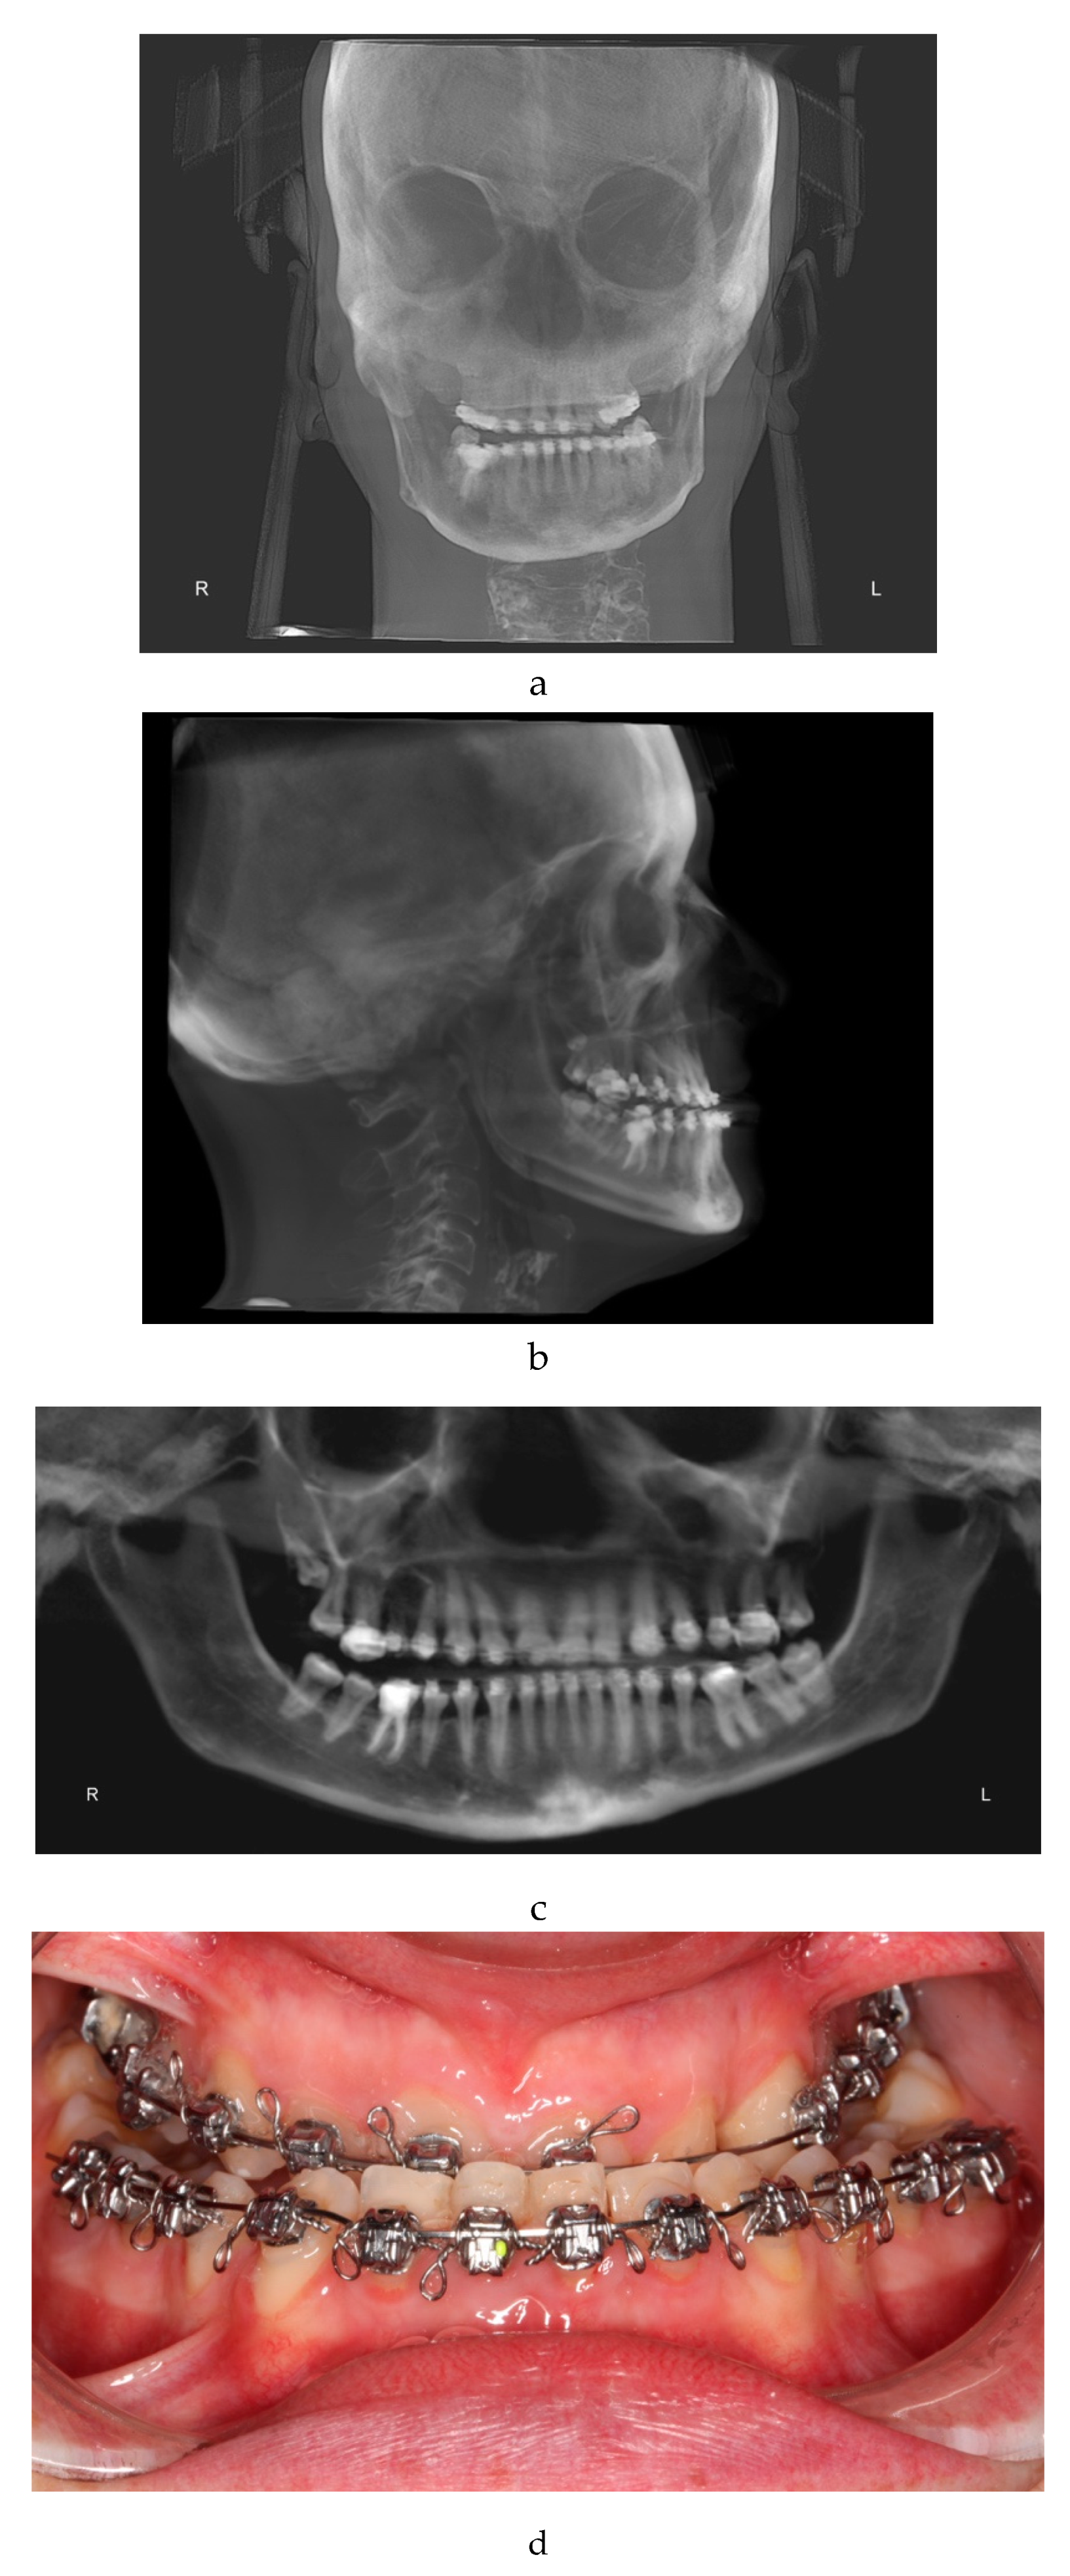

The x-ray examination through cone beam computed tomography (CBCT) [22] (Figure 1a, 1b, 1c) processed with dolphin software [23] showed:

- Third skeletal class

- Hyperdivergent skeletal profile

- Left lateral deviation of the mandible

- Contracted upper arch

- Inclusion of 15 in a transverse position, near the apexes of elements 1.4 and 1.6.

Figure 1. a: antero-posterior projection of the CBCT. b: lateral-lateral projection of the CBCT. c: panoramic projection of the CBCT.